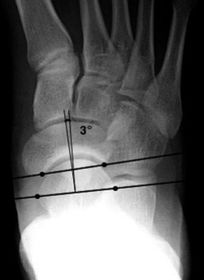

| What is this angle called? Is this normal or abnormal? | AP - Talo-calcaneal angle This is normal |